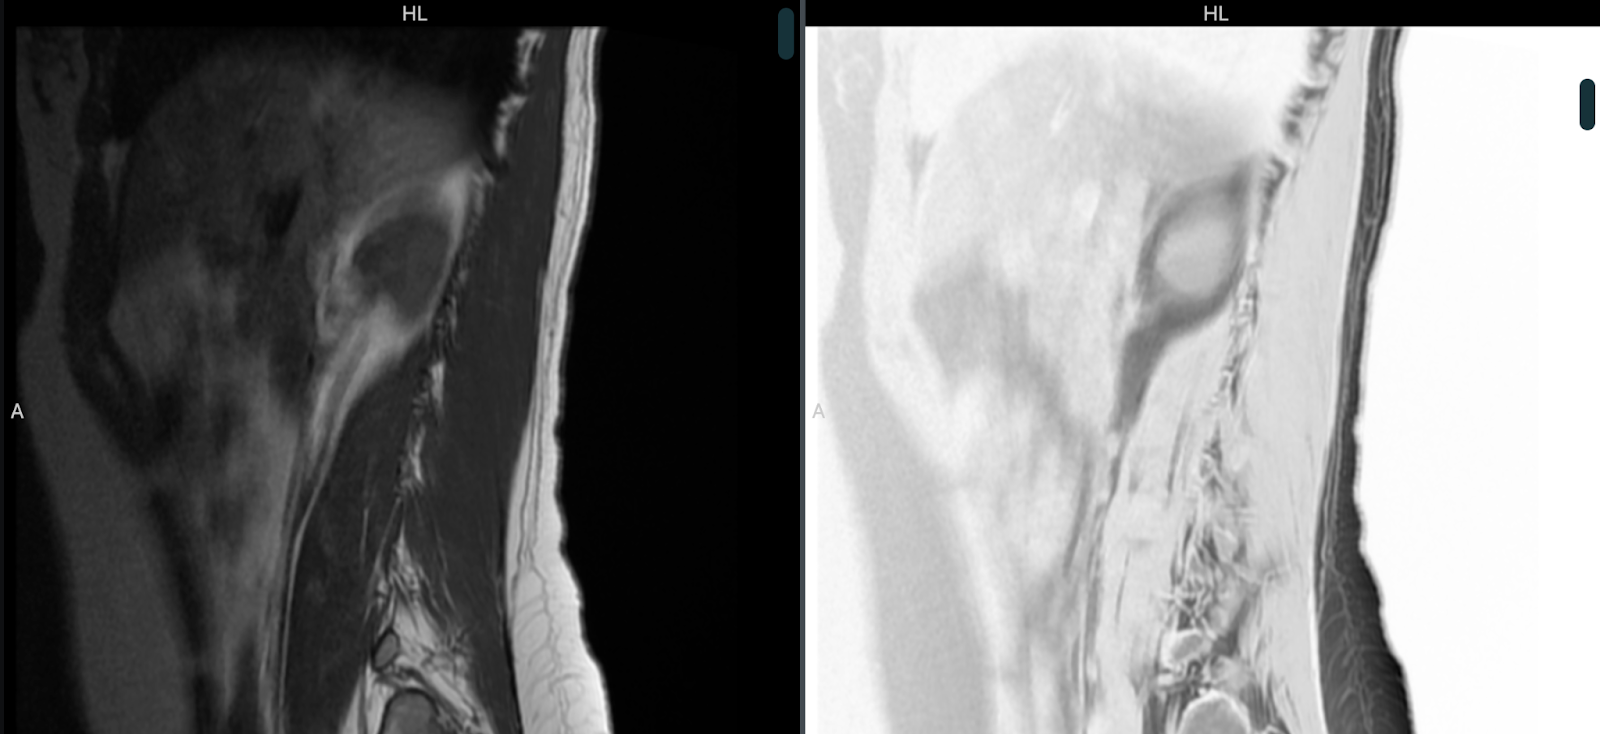

Modo cine:

En esta sección, tenemos dos submenús. El modo cine nos sirve para visualizar las imágenes generadas por un estudio como TAC o RMI en secuencia. Al seleccionarla nos aparecerá un control de desplazamiento de estilo película con el cual podremos avanzar, retroceder, reproducir o cambiar la velocidad de reproducción de la secuencia, como lo muestra la siguiente imagen:

MPR: Herramienta de reconstrucción multiplanar. Permite reconstruir los cortes axial, coronal y sagital a partir de solo una serie de imágenes. En la siguiente imagen podemos ver la ubicación de los íconos exclusivos de esta herramienta.

Las herramientas de MPR se explican en la siguiente sección:

Herramienta de punto de mira: Al seleccionarla, permite enfocarnos en un punto de mira en la imagen. Al centrarnos en ese punto, en los otros cortes se mostrará la ubicación de forma sincronizada.

Cambiar grosor de corte: El cambio de grosor del corte se puede hacer por el deslizador, cambiando la medida de forma numérica, o ajustando con el punto de control en los ejes coloreados.

Generar vista oblicua: Al tomar este punto de control y rotarlo con el mouse, podemos oblicuar alrededor del punto de mira seleccionado.

Selección de proyección: Al ajustar un ancho de corte suficiente, podremos seleccionar entre la proyección de máxima intensidad, proyección de intensidad media, o proyección de mínima intensidad.